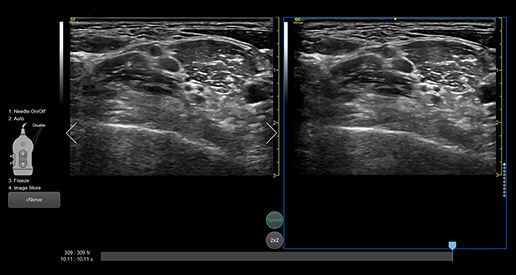

Follow nerve block procedures with cNerve

Helps detect and track nerves in 99% of cases during live scanning or while reviewing a stored clip2 while also displaying a distribution map of the areas on the body impacted by the selected nerve block procedure.